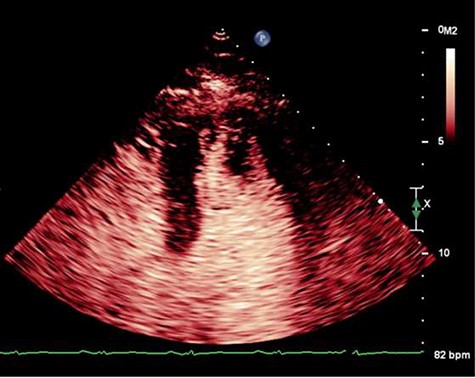

On Day 13, he developed acute global aphasia. Contrast echocardiography confirmed persistence of the same LV thrombus which had indeed increased in size despite 1 week of oral anticoagulation (Fig. 1). Given concerns for risk of haemorrhagic transformation of a recent ischaemic stroke with thrombolysis, a multi-sdisciplinary decision was taken to proceed to surgical thrombectomy.